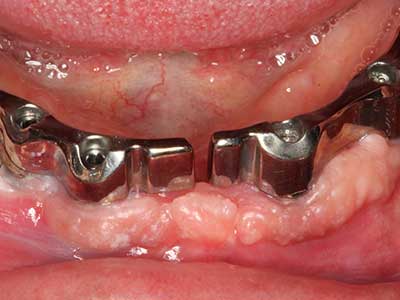

Marginale Parondontalerkrankungen stellen im fortgeschrittenen Alter den Hauptgrund für Extraktionen dar. Sie basieren im Wesentlichen auf einer bakteriellen Besiedlung der Zahnfleischtasche und hierdurch bedingten Entzündung mit konsekutivem Verlust des Zahnhalteapparates. Die Ausbildung subgingivaler Biofilme und Konkremente stellt einen wesentlichen ätiologischen Faktor für den marginalen Knochenabbau dar, so dass ihrer Entfernung eine wesentliche Bedeutung in der Therapie zukommt (Drisko 2014, Plessas 2014).

Zur Behandlung einer marginalen Parodontitis lassen sich eine initiale und chirurgische Therapiephase unterscheiden. Neben der Mundhygieneinstruktion und -motivation sollte in beiden Phasen eine suffiziente Reinigung der Wurzeloberfläche erfolgen, wobei im regenerativen Setting zumeist ein offener Zugang gewählt wird. Die Reinigung der Wurzeloberfläche kann durch die Verwendung spezieller Ansätze auch piezochirurgisch erfolgen, wobei unterschiedlich gebogene Instrumente auch schlecht zugängliche Bereiche wie Furkationen erreichen. Die systemimmanente Wasserkühlung spült dabei die gelösten Konkremente und Bakterien aus der Tasche. Um zusätzlich die Abtragung von Zahnhartsubstanz zu minimieren, wurde bei speziellen Systemen wie dem Piezomed ein Applikations-Feedback eingebaut. Hierbei wird die Abtragungsleistung konsequent reduziert, je mehr Druck auf den Parodontalansatz ausgeübt wird.